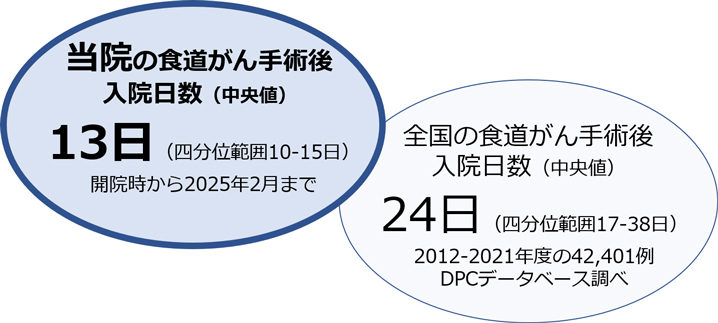

食道がんや胃がんの手術後には肺炎や縫合不全などの合併症をきたすことがあります。合併症が発生すると入院期間が長くなるだけでなく、退院後の回復具合にも影響を与える可能性があります。当院では東京大学・慶應義塾大学・国立がん研究センター中央病院と共同でDPCデータベースという全国規模のビッグデータを用いて、術後合併症のリスクを最小化するための様々な周術期管理(手術前から手術後の治療的サポート)を研究し、その成果を国内学会・メディアのみならず世界のトップジャーナル(米国や英国の一流外科医学雑誌)で発表しています。

当チームの日常診療にもその成果をいち早く導入し、非常に良好な成績を残しています。例えば、当チームで手術された食道がんの患者さまは全国の平均的な施設よりも11日間早く退院(回復)されており、全国でもトップクラスです。